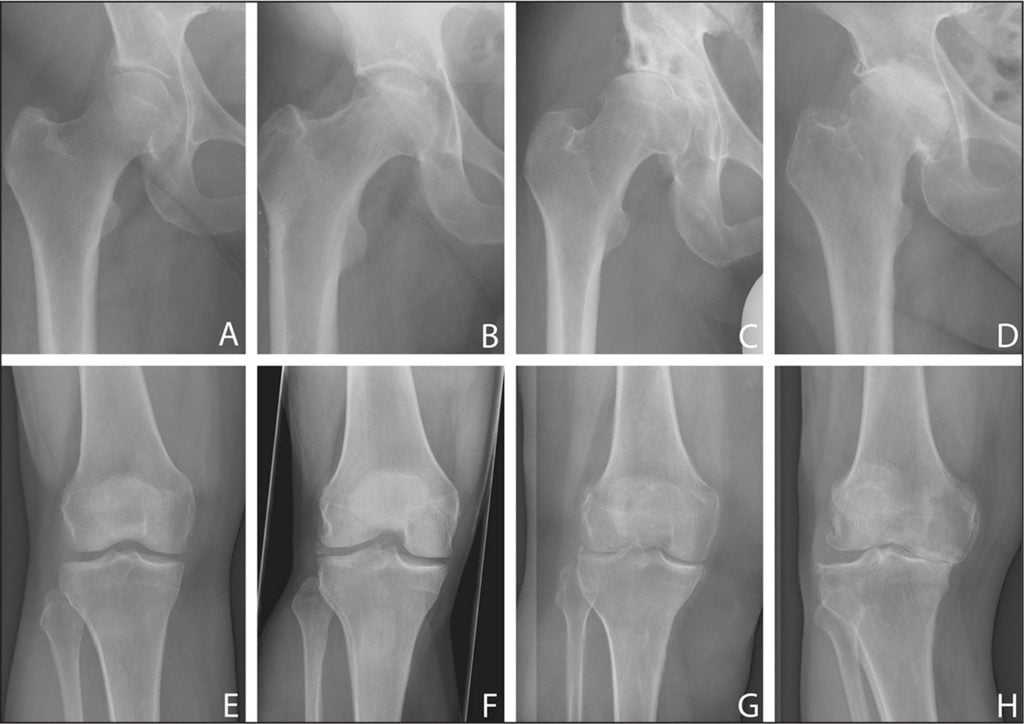

Уменьшение суставной щели.

Динамика болезни.